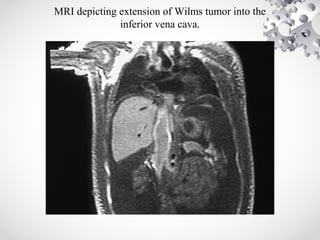

• MRI ABDOMEN:

Most sensitive imaging modality for caval

patency, to determine tumor extension into

IVC.

low signal intensity on T1-weighted images

and high signal intensity on T2-weighted

images.

MRI depicting extension of Wilms tumor into the

inferior vena cava.

• MRI ABDOMEN: Mostsensitive imaging modality for caval patency, to determine tumor extension into IVC. low signal intensity on T1-weighted images and high signal intensity on T2-weighted images.

MRI depicting extensionof Wilms tumor into the inferior vena cava.